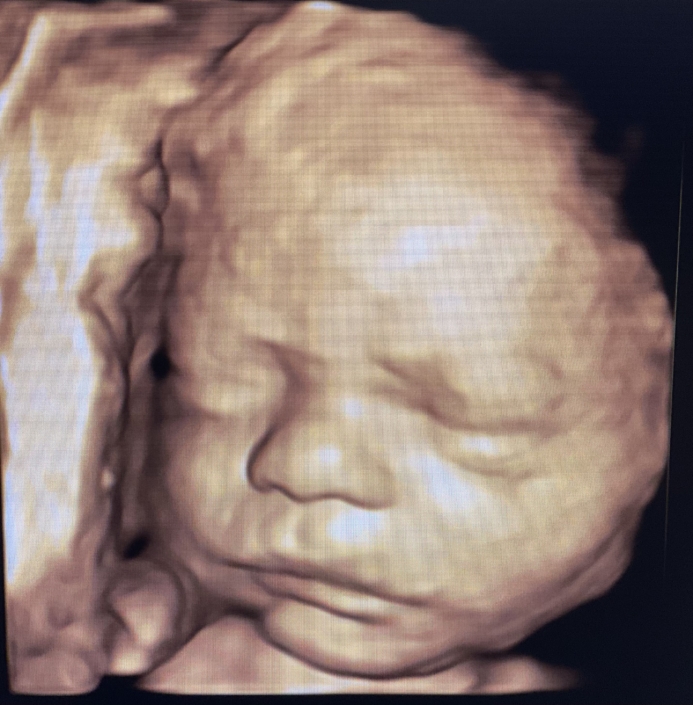

Prenatal Peek®

Prenatal Peek is the leader in 3D 4D Ultrasound. We employ only Certified / Registered Sonographers maintaining unsurpassed standards in 3D ultrasound. You deserve the best! Call us today.